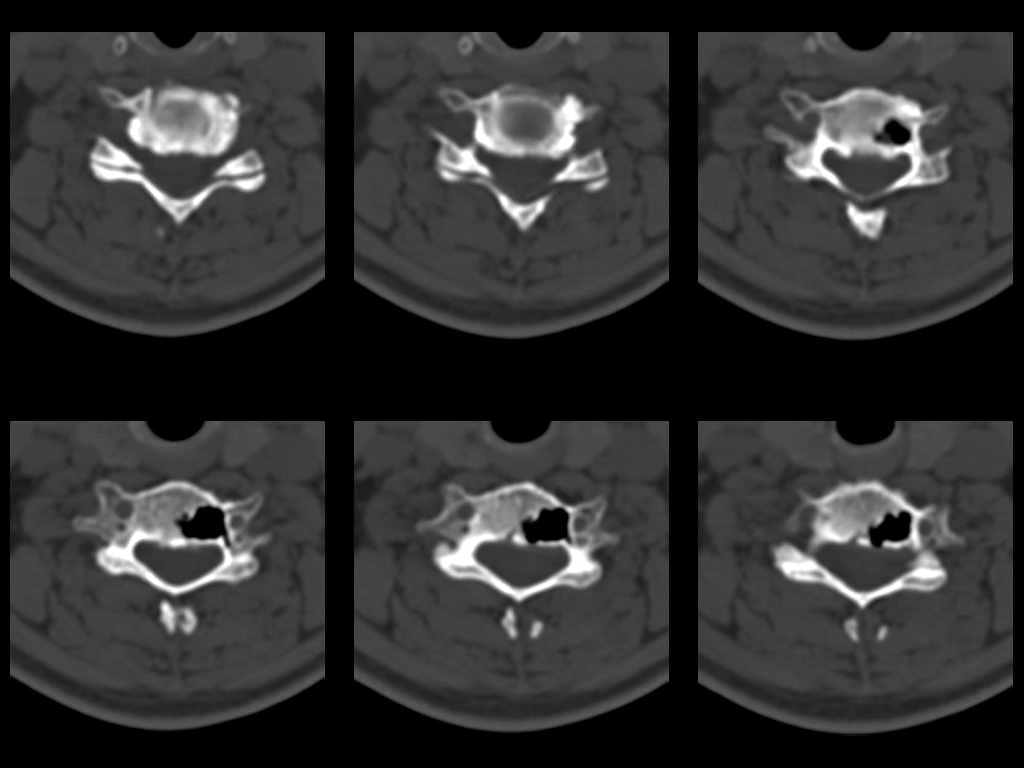

У женщины 49 лет, при рентгенографии шейного отдела в теле С6 выявлен участок деструкции.Часть N1 Больная находилась в неврологическом отделении с диагнозом энцефалопатия. Была проведена КТ тела С6, 26.12.2002 выявлен участок деструкции 0,9х1,2 см, плотность участка составляет -1022 ед.Н. аналогичная плотности воздуха в трахее.Возникает вопрос что это? Метастаз, киста,или какой то вредный анаэроб грызет тело позвонка?Через пол года 03.06.2003 произведено повторное исследование. Отмечается отрицательная динамика. Участок деструкции увеличился в размерах, увеличелась площадь разрушения задней поверхности тела С6.

Наличие выраженных дистрофических изменений, а также сообщение полости в теле позвонка С6 с полостью межпозвонкового диска в сегменте С5-С6, а также наличие газа в полости межпозвонкового диска С5-С6 спереди, на границе фиброзного кольца и пульпозного ядра (3-й слева срез в нижнем ряду на второй из представленных КТ) делает диагноз остеохондроза, осложненного вакуум-феноменом и прорывом газа в полость тела позвонка с формированием воздушной кисты (пневмкисты) несомненным.

Первые 2 серии снимков это от 2002г, вторые 2 серии от 2003 г. Относительно размеров, сообщю дополнительно все перермерю на томографе.

Размеры за 2002 год 1,2х0,9х1,2 мм

за 2003 1,3х0,9х1,2 мм. Но контур деструкции стал более неровный и внедрение в дужку С6 увеличелось.

Характер процесса не вполне ясен. Учитывая скопление газа на фоне тела

позвонка, с наибольшей вероятностью - "вакуум-феномен" в следствии

дегенерации межпозвонкового диска. Наложение газа на образование в теле

позвонка (гемангиома?) создает затруднение в диагностике (по-видимому